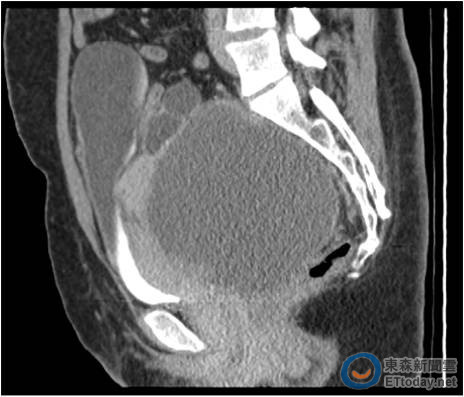

▲子宮內膜異位忍20個月才就醫,「巧克力囊腫」變卵巢癌。(圖/台北醫學大學附設醫院提供)

一名38歲的婦女有卵巢子宮內膜異位瘤,雖然動過3次手術,但在第4度復發時因症狀無明顯不適,拖了20個月才就醫,經醫師診斷,已經轉變成14公分的惡性卵巢癌,由於沾黏過度嚴重,最終仰賴達文西手術,才將子宮、卵巢與淋巴的腫瘤切除,術後仍需接受化療。